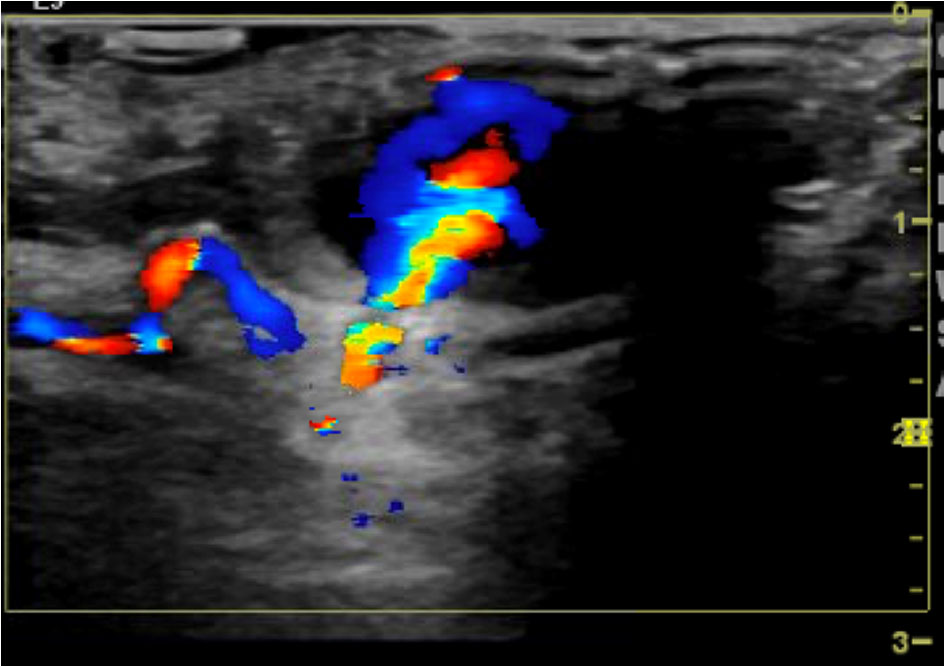

An 82-year-old woman with hypertension and atrial fibrillation on warfarin presented with 2 h of acute onset epigastric pain with radiation to the chest, jaw, and left arm. Initial vitals were within normal limits. She was in moderate distress. Labs were significant for a subtherapeutic international normalized ratio (INR). Electrocardiogram revealed ST segment elevations in the inferolateral leads. After Allen’s test was done, she was deemed an appropriate candidate for approach via right radial artery and taken for urgent cardiac catheterization. The patient was found to have an acute thrombus in the distal posterior descending artery (PDA) and posterior left ventricular (PLV) branch. She was treated with angioplasty and aspiration thrombectomy, and the acute thrombi were thought to be secondary to thromboembolic phenomenon. The patient received dual antiplatelet therapy following the procedure, and a pneumatic band was placed over the patient’s right wrist and remained in place until it was removed per protocol. The following day, patient reported pain at the right wrist. On exam, a pulsatile 2.4-cm mass with an overlying bruit was noted. A color flow Doppler ultrasound study was performed and it revealed a radial artery pseudoaneurysm (Fig. 1). Initial discussions with vascular surgery, and interventional radiology did not yield a consensus approach towards resolving this complication. Nonspecific compression via pneumatic band was attempted for 18 h; however this was initially proved unsuccessful as seen on repeat Doppler. Following this, a different compressive approach was attempted. Pneumatic band was inflated until radial pulse flow was occluded as evidenced by absence of pulse oximetry wave form. The level of occlusion was achieved with 12 cc of air inflation. Air was removed in small segments until radial artery flow was noted (this was noted to be at 10 cc of air inflation of the pneumatic band). Upon dialogue with nursing staff, it was discussed that the pneumatic band should remain in place at current level of compression for 1 h and then 1 cc of air should be removed each hour until device was fully deflated (Table 1). After the allotted time course of 10 h that it took to deflate the pneumatic band, a repeat arterial Doppler ultrasound revealed complete resolution of the radial pseudoaneurysm (Fig. 2). She also reported improvement of pain, and was discharged that day.

![]() Click for large image | Figure 1. Duplex ultrasound demonstrating patent right radial artery with a pseudoaneurysm just measuring 2.3 cm × 2.4 cm × 1.4 cm, and the neck of the pseudoaneurysm measuring 2.1 mm. |